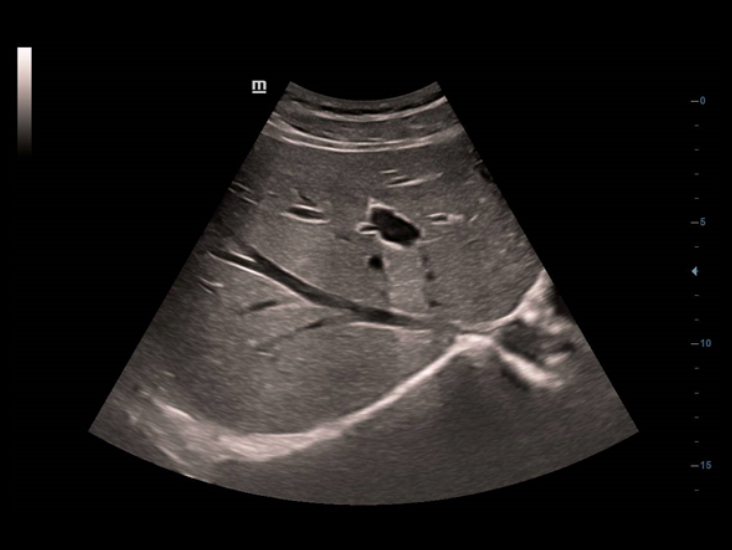

Full HD es una soluciĂłn progresiva destinada a satisfacer los requisitos de personas como usted, plenamente comprometidas con ofrecer un servicio de atenciĂłn primaria de la mĂĄxima calidad. Se considera que, incluso en condiciones limitadas, un sistema de diagnĂłstico por ultrasonido debe poderle ofrecer claridad de imagen, facilidad de uso y fiabilidad.

Como primera representante de la gama Full HD, el DC-40 con Full HD es la respuesta ideal a sus requisitos clĂnicos. El objetivo del concepto Full HD es ofrecer prestaciones excepcionales a los usuarios de sistemas de diagnĂłstico por ultrasonido, por ejemplo una definiciĂłn de imagen superior, un dise?o ergonĂłmico mejorado y una fiabilidad superior.

Mediante la aplicaciĂłn de tecnologĂas de obtenciĂłn de imĂĄgenes clĂĄsicas, que se migran de sistemas de diagnĂłstico por ultrasonido consolidados, el DC-40 con Full HD le proporciona una mejor calidad de imagen con el grado de detalle que necesita.